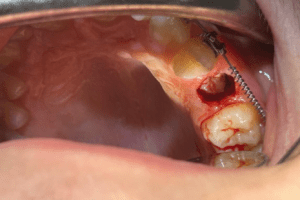

Successivamente, in combinazione con la terapia precedentemente stabilita, abbiamo optato per una esposizione con elettrobisturi in modo da permettere al dente la sua normale eruzione. Questa procedura consente un approccio meno invasivo, meno doloroso, previene il sanguinamento, evita la diffusione di batteri e protegge meccanicamente la struttura tissutale; la cicatrizzazione inoltre sarà più rapida e non sarà necessario l’utilizzo di punti di sutura. Il paziente avrà così un recupero più rapido e con maggior confort.